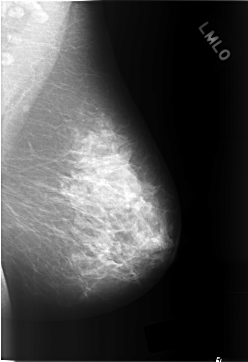

C_0304_1.LEFT_MLO

LEFT_MLO LINES 5792 PIXELS_PER_LINE 3968 BITS_PER_PIXEL 12 RESOLUTION 50 NON_OVERLAY

RIGHT_MLO LINES 5816 PIXELS_PER_LINE 4088 BITS_PER_PIXEL 12 RESOLUTION 50 OVERLAY